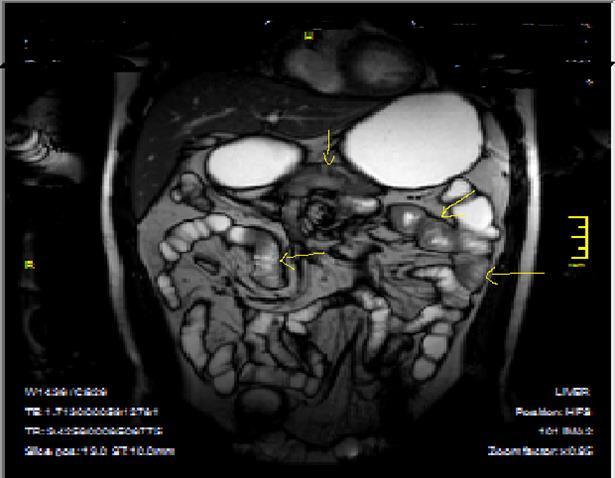

Bowel wall thickening with increased luminal and extra-luminal signal changes on FS images, showing active inflammation, edema in the adjacent intraperitoneal and mesenteric spaces, active inflammation; bowel wall thickening and enhancement on post-contrast T1W images plus high signal intensity on T2W- FS images7, 9, 12, 14, 17, 18, 19, 20, 21 (Figure 4a-b).

Chronic disease without active inflammation; Bowel wall thickening and enhancement on postgadolinium T1W images plus low signal intensity on T2W-FS images with possible stenosis and obstruction due to fibrosis, chronic disease with active inflammatoryexacerbations;these conditions can overlap with active inflammation, require longitudinal repeated scanning7, 12, 14, 20,26, 27, 28, 29, 30 (Figure 5a-b, Figure 6a-b)

Figure 4a.Mucosal involvement and lack of opacified ileal segments with loss of intestinal folds and increased bowel wall thickness due to Crohn’s disease on T2W coronal sequence after OCA, presented at 37 years old male with moderate Crohn’s disease.

Figure 4b.Mucosal, luminal and bowel wall involvement in Crohn’s disease with skipped lesions, seen at T2W axial image after OCA, presented at 45 years old male with severe inflammatory disease.